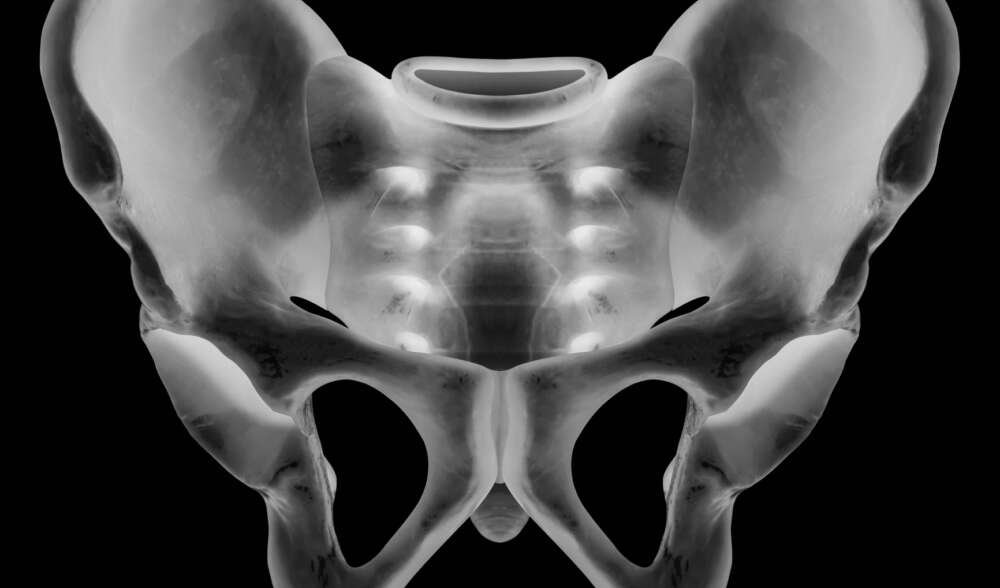

Fraktur der linken Seite des Sakrums auf Höhe von S1